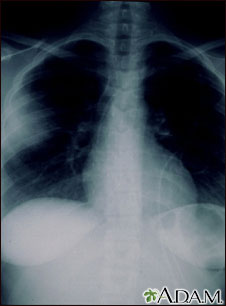

Aspergillosis is a fungal infection. The fungus invades and destroys tissue. This type of infection usually occurs in immunocompromised individuals. Here, a chest x-ray shows that the fungus has invaded the lung tissue. The lungs are usually seen as black areas on an x-ray. The cloudiness on the left side of this x-ray is caused by the fungus.